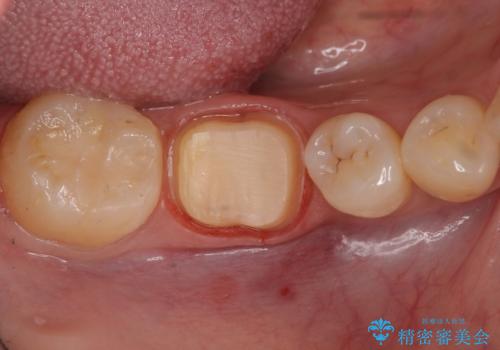

虫歯の除去後は残った歯の厚みが薄くなっていたため、今後の破折リスクを考慮してクラウンでの修復処置となりました。

虫歯が深く歯の神経の炎症が予想される箇所には鎮静作用のあるセメントを敷き、経過をみた後に被せ物をセットしました。

写真・レントゲン画像からもわかる通り、適合の良いクラウンを入れることができました。